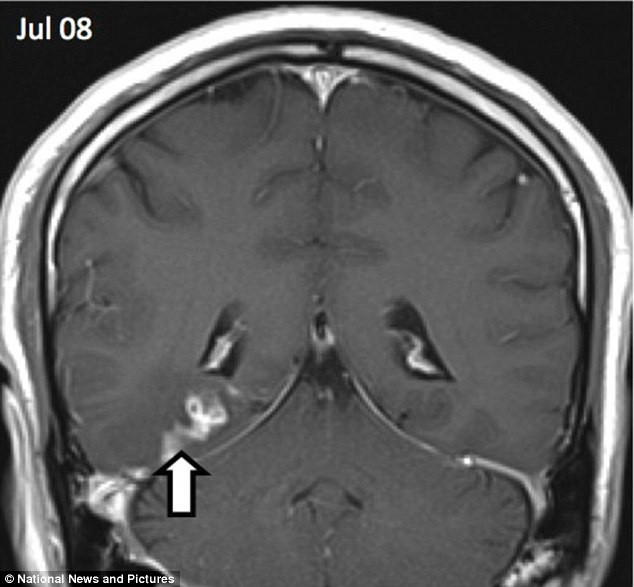

Hình chụp X-quang của một người đàn ông cho thấy anh ta đã bị một con sán dây dài 1cm đào sâu tới 5cm vào não từ trái qua phải.

Sán dây dài 1cm sống trong não người đàn ông trong suốt 4 năm ảnh 2Con sán dài 1cm đã đào sâu tới 5cm vào não bệnh nhân. (Nguồn: DM)